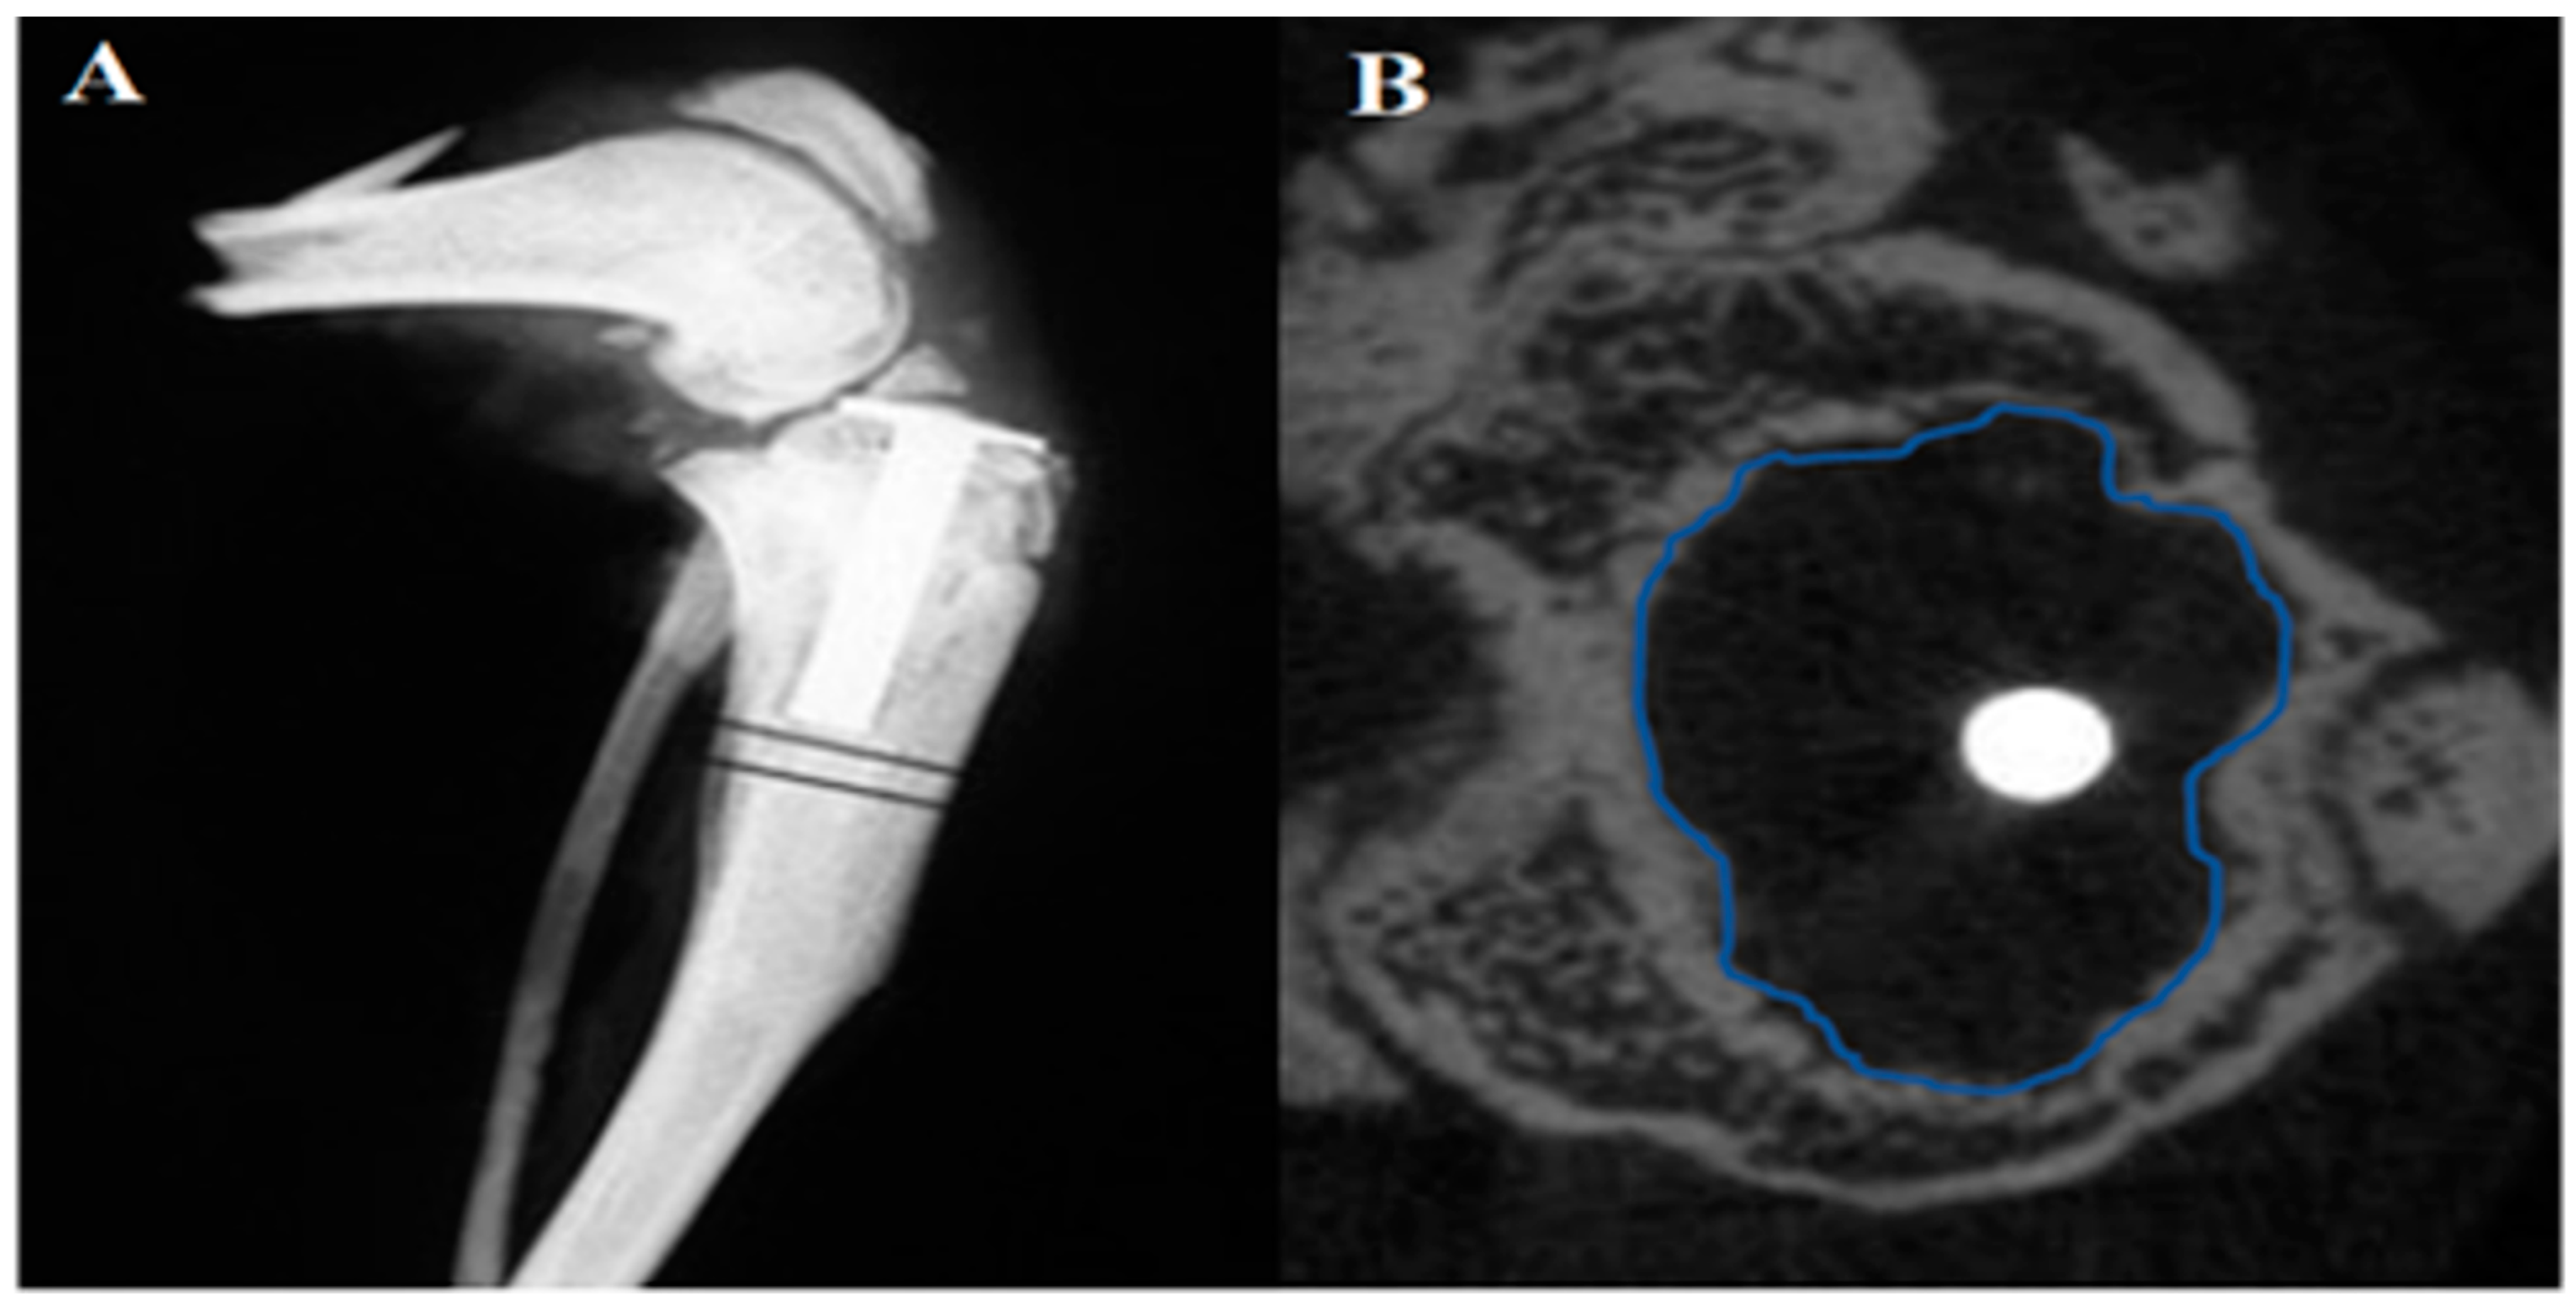

2.3. μCT Evaluation of Osteolysis

4.5. Evaluation of Periprosthetic Osteolysis by Micro-Computed Tomography (μCT)